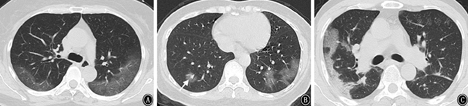

2组CT影像学基线资料比较见表2。A组支气管血管束及外周混合分布明显多于B组(χ2=32.705,P<0.001);B组胸膜下外周分布明显高于A组(χ2=13.268,P<0.001)。见图1、图2。

注:白色箭头示磨玻璃影结节伴血管影增粗

早期征象最常见的是GGO,总检出率96.9%(63/65),A、B组GGO检出率无明显差异(χ2=2.420,P=0.120)。"细网格"征共检出32例(49.2%),A、B组的检出率分别为75%(12/16)和40.8%(20/49),差异有统计学意义(χ2=4.201,P=0.04)。以反晕征为主要表现的共检出8例(12.3%),A、B组的检出率分别为18.8%(3/16),10.2%(5/49),差异无统计学意义(χ2=0.608,P=0.436),但有1例危重症患者早期表现为多发性GGO和反晕征,48 h后病灶明显进展形成肺实变(图3)。病灶内血管影增粗,共检出47例(72.3%),A、B组的检出率分别为87.5%(14/16)和67.3%(33/49),差异无统计学意义(χ2=1.160,P=0.281)。

COVID-19的影像学早期征象以双肺多发GGO最为常见,这与SARS-Cov-2感染后引起肺泡壁的损伤、血管的充血和肺泡间隔的水肿有关[10]。本研究尝试对COVID-19患者的首次胸部HRCT进行分析后有如下发现。(1)病变在48 h内出现快速进展者的基线影像学特征表现为:病变多发、呈支气管血管束及外周混合分布、"细网格"影和病灶的边界模糊。这部分患者外周血淋巴细胞、CD4+T细胞减少,免疫功能低下,病灶不易局限,更易沿支气管血管束的轴向进展和蔓延[11]。而且由于淋巴细胞向靶器官迁移,导致局部的炎症反应明显使病灶的边界较为模糊。"细网格"征的检出率比较高,与SARS-Cov-2感染引起小叶间隔和小叶内间质增厚有关。(2)非快速进展者的基线影像学特征表现为:外周胸膜下外周分布的GGO、病灶边界清楚的多见。最常见分布区域的是两下肺基底段和背段,这是由于下肺和外周胸膜下区肺小叶的血流和淋巴管网分布丰富,相应小叶间质的炎性反应也更明显[12]。COVID-19病变的进展模式为以肺小叶为单位向外融合扩展,受小叶结构阻挡故而表现为具有一定的边界。推测这部分患者局部炎症反应相对较轻,病灶具有一定的自限倾向。(3)"反晕征"的检出率较低,但是曾有1例早期以多发性支气管血管束分布"反晕征"为主要表现,后期发展为肺实变的危重型病例,不排除SARS-Cov-2感染继发机化性肺炎的可能,需要引起临床足够的重视[13]。"血管影增粗"征检出率高,该征象在近期COVID-19的相关文献中也有报道[14,15],并且发现增粗的血管走行僵硬,边缘欠光整,考虑与病毒侵犯血管内皮细胞和肺泡毛细血管网,引起的血管炎有关[16]。但这两个征象与病灶的进展模式无明显相关性。